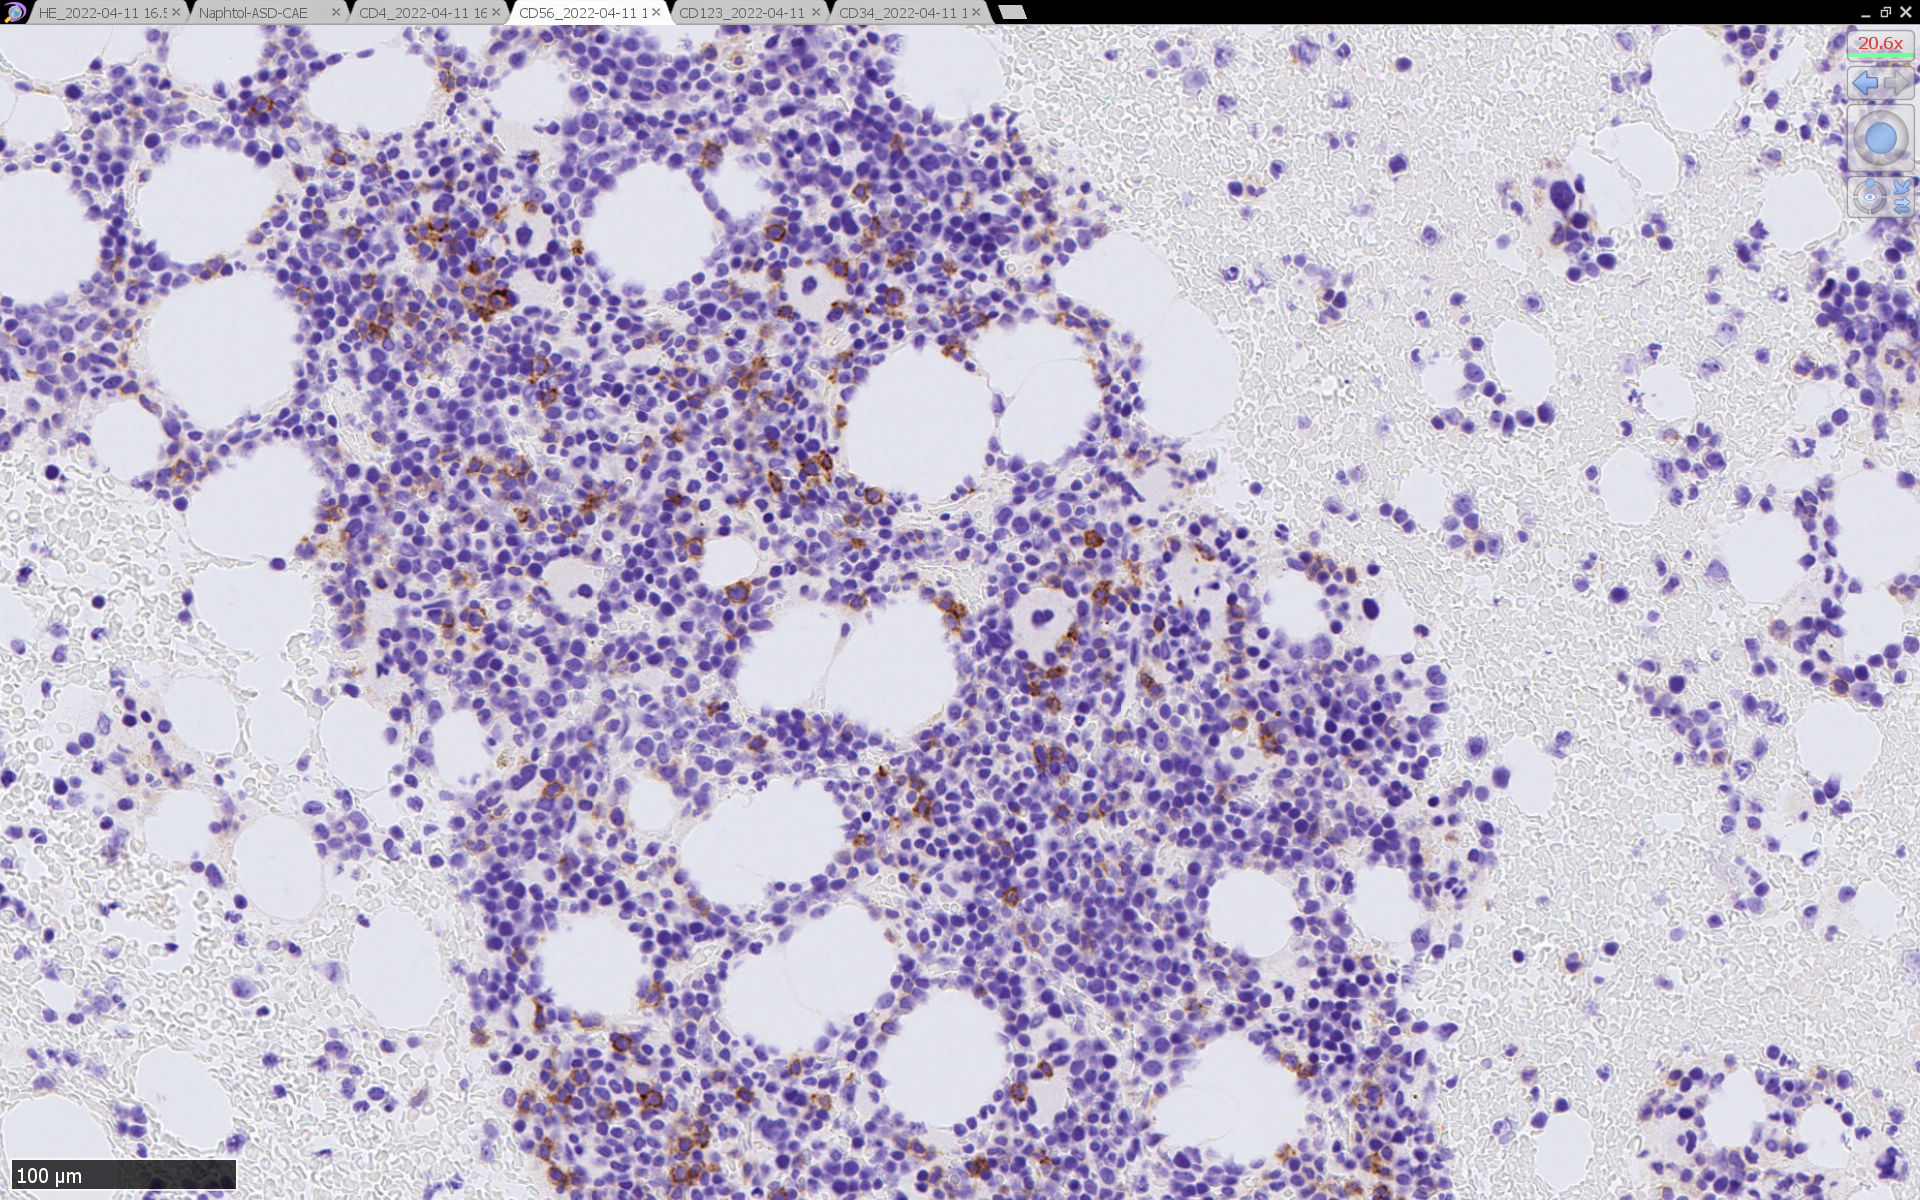

骨髄病理所見

HEでは腫瘍細胞の同定が難しい. 本症例は ASD-Giemsa染色を見ても, 腫瘍胞巣はよくわからなかった. 皮膚が先に診断がつき, 次いでBone marrowだったため, 免疫染色にすすめたが, Bone marrowが先だと診断に困ったかもしれない.

免疫染色

CD4は染まりすぎの感がある(濃く染まる細胞はCD4+ T-cellかもしれない). CD56, CD123が陽性で可能性が高くなり, BPDCNの診断にはCD34は陰性であることが必要

TCF4、CD123、TCL1をconsultationにより染色していただき, 陽性を確認した. CD34-, lysozyme-, CD123(おいてある病院は少ないかも)をしらべて, BPDCN研究会あてconsultationをする流れでしょうか.